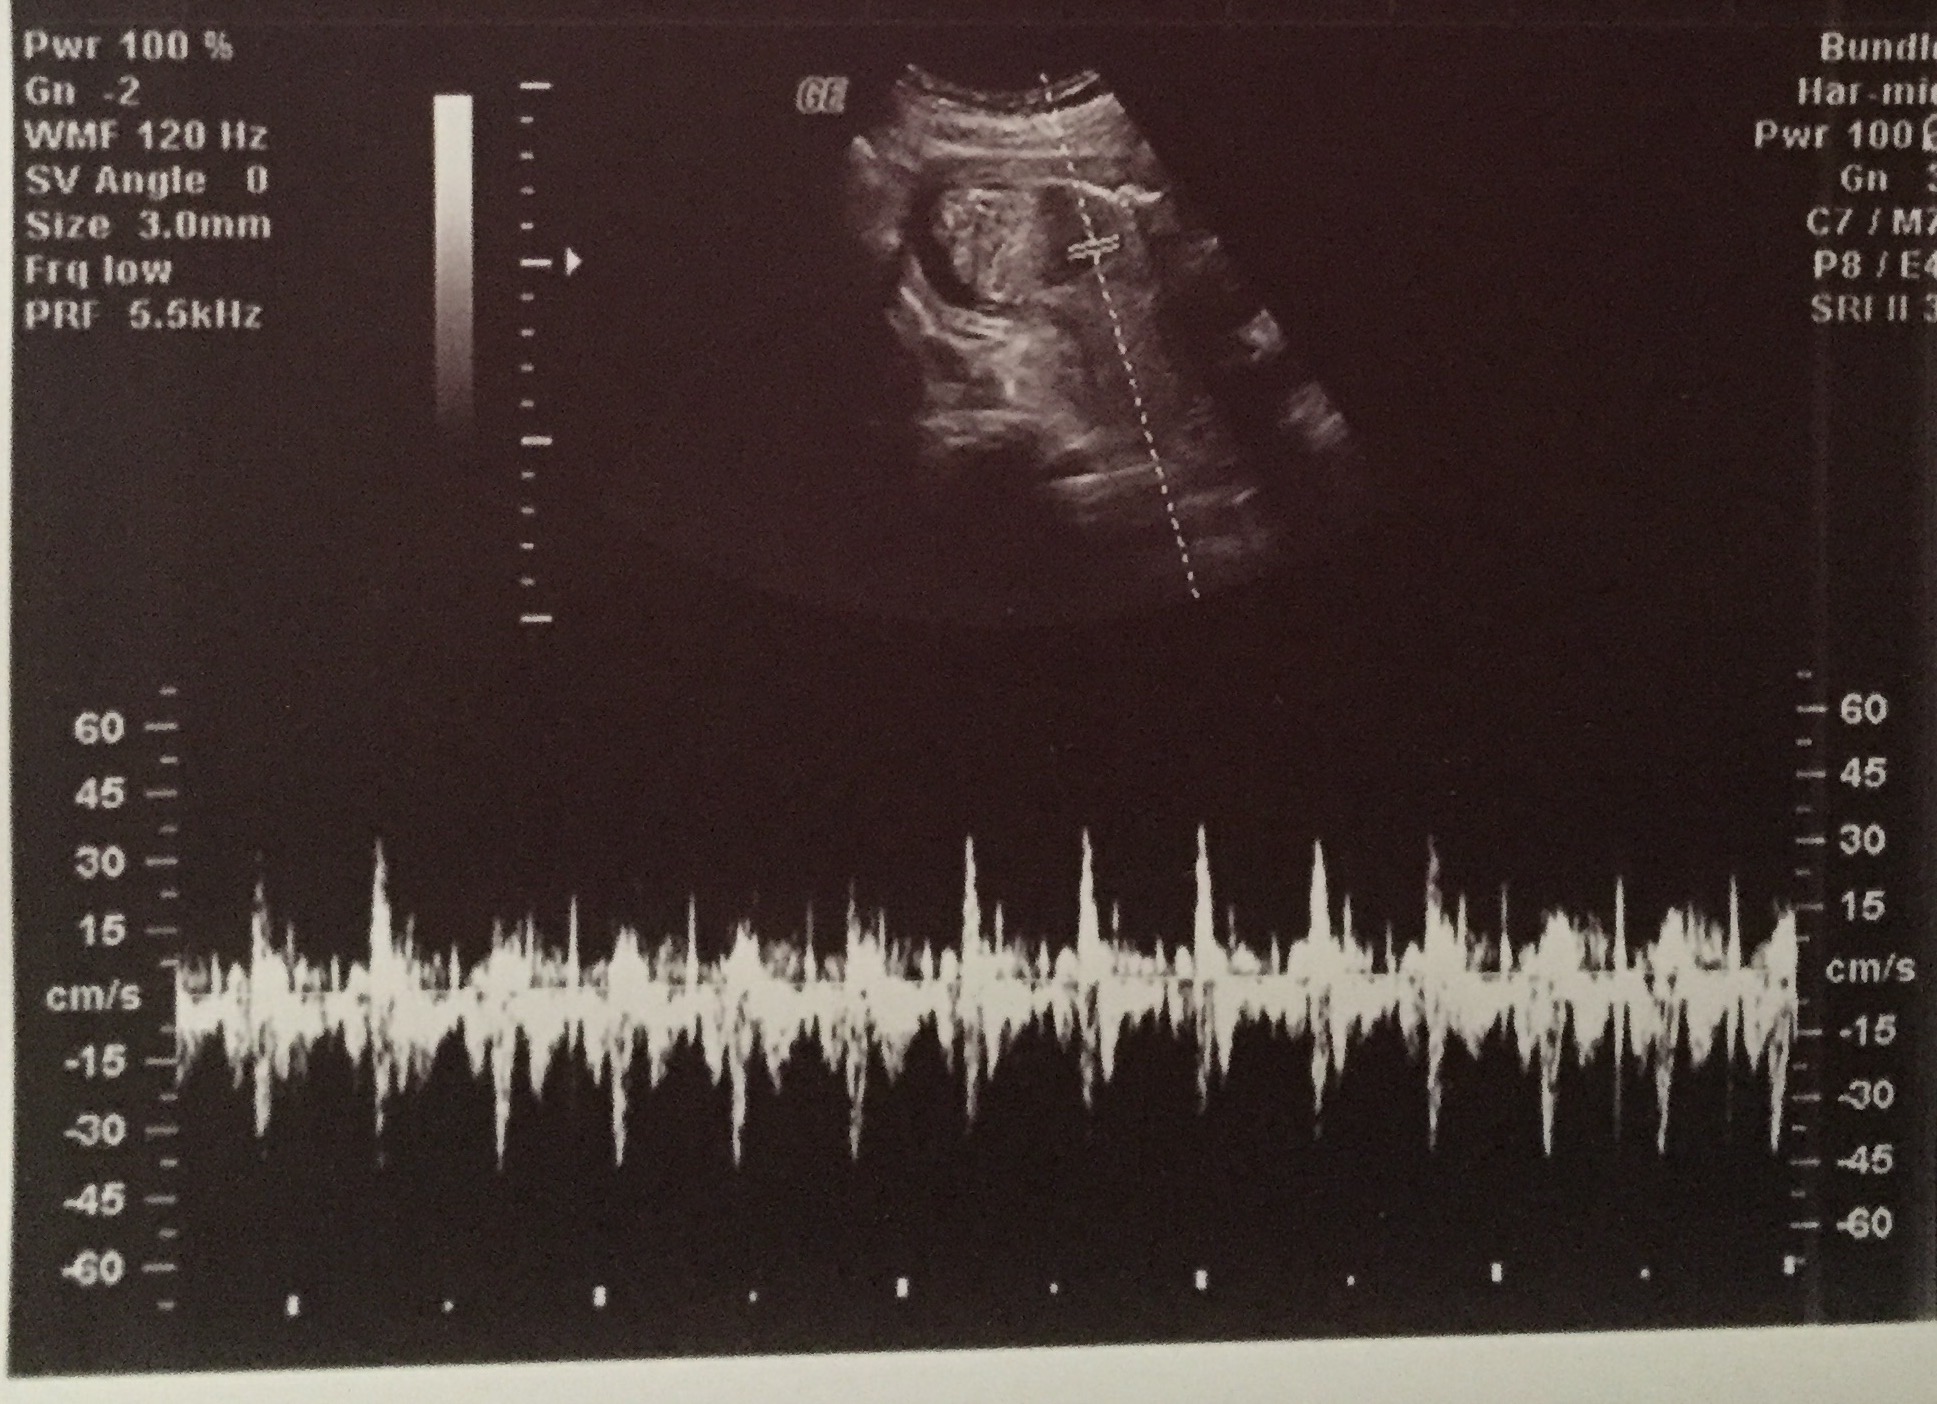

I had an elective 2d/4d ultrasound done at 16 weeks and 3 days to determine the gender of my baby. The baby wasn't all that cooperative and had the umbilical cord between its legs. It moved it's legs for a second and the ultrasound technician said that she saw the "hamburger buns" (labia). She also said that she saw the three white lines of the vaginal bones multiple times and that she felt confidant it was a girl. However, she could not get me a clear picture of the genitals in 3d because the baby would not move it's leg again to give a clear view of it's parts. She took this picture (1st picture) in 2d of what is the supposed white lines. I am just looking for opinions on whether this looks like a baby girl or if it could be a boy because I don't want to tell my whole family and then be surprised at my 19 week scan when they say it's a boy. The pictures are big, I'm not sure how to make them smaller.

Attachment 35760